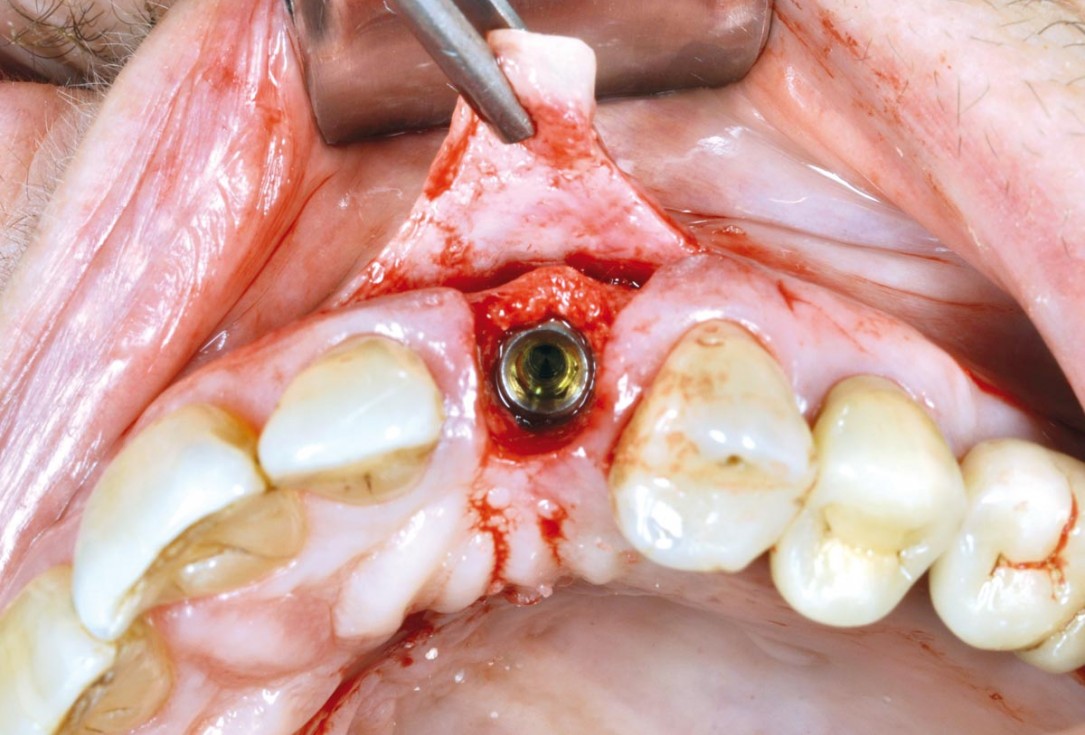

GBR with cerabone® and Jason® membrane in the front tooth region - Dr. H. Maghaireh

Initial clinical situation with gum recession and labial bone loss eight weeks following tooth extraction